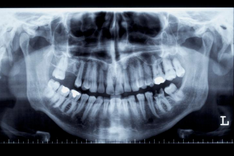

임플란트 가격 시술과정 등 정보에 대해 알아보도록 하겠습니다. 임플란트는 손상된 이빨이나 빈 치아를 대체하기 위한 인공 이빨입니다. 일반적으로 작은 나사 모양의 금속 장치로, 잇몸과 안면골 사이에 삽입됩니다. 이 장치는 실제 이빨과 동일한 역할을 수행하고, 씹기, 말하기 및 웃음을 할 때 자연스러운 모습을 유지합니다.

임플란트 수술은 전문적인 치과 의사나 구강 외과 전문의에 의해 수행됩니다. 일반적으로 수술 후 임플란트는 몇 개월 동안 치아와 함께 인공 잇몸으로 덮여 골이 잘 결합되도록 하고, 그 후에 인공 이빨이 부착됩니다.

- 치과 의사와의 상담 및 검사: 치과 의사와의 상담을 통해 환자의 상태와 필요한 수술 범위 등을 확인합니다. 검사를 통해 치아와 관련된 질병이나 문제를 파악할 수 있습니다.

- 임플란트 삽입: 치과 의사는 임플란트를 안정적으로 삽입하기 위해 잇몸을 절개하고, 임플란트를 치아 뼈에 삽입합니다. 수술 후에는 굳게 고여있는 결손을 채우기 위해 뼈 이식이 필요한 경우도 있습니다.